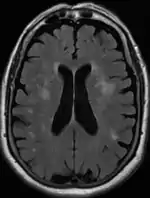

Axial T2 FLAIR sequence MR image of a middle-aged man with leukoaraiosis.

Leukoaraiosis is a particular abnormal change in appearance of white matter near the lateral ventricles. It is often seen in aged individuals, but sometimes in young adults.[1][2] On MRI, leukoaraiosis changes appear as white matter hyperintensities (WMHs) in T2 FLAIR images.[3][4] On CT scans, leukoaraiosis appears as hypodense periventricular white-matter lesions.[5]

These white matter changes are also commonly referred to as periventricular white matter disease, or white matter hyperintensities (WMH), due to their bright white appearance on T2 MRI scans. Many patients can have leukoaraiosis without any associated clinical abnormality. However, underlying vascular mechanisms are suspected to be the cause of the imaging findings. Hypertension, smoking, diabetes,[3] hyperhomocysteinemia, and heart diseases are all risk factors for leukoaraiosis.